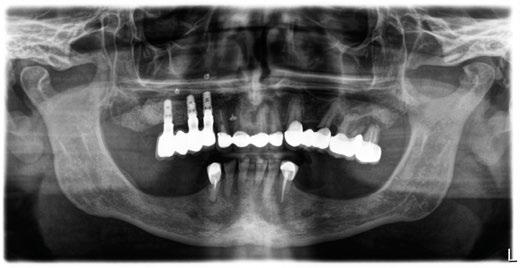

-Estudio radiográfico inicial (ortopantomografía y radiografías periapicales) (Figura 2).

Figura 2. Ortopantomografía inicial.

Figura 27. Ortopantomografía del provisional atornillado en boca para verificar ajuste.

ortopantomografía de verificación del ajuste pasivo de todos los implantes. Por último, tapamos las chimeneas con teflón y resina provisional y se chequeó nuevamente la oclusión, dando nuevamente las instrucciones de higiene y mantenimiento de la prótesis provisional (Figuras 24-27).